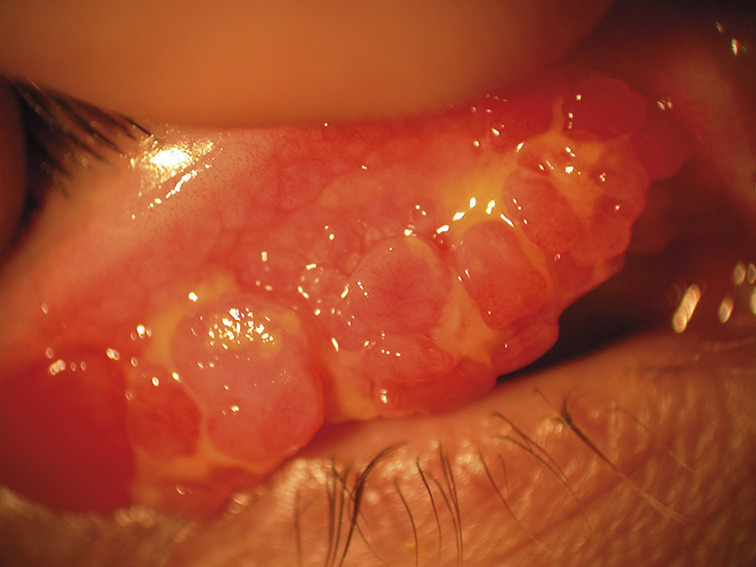

L’atteinte souvent bilatérale n’est pas toujours symétrique. La kératoconjonctivite vernale est caractérisée par la présence de papilles géantes (diamètre > 1 mm) sur le versant tarsal de la conjonctive (fig. 1 ). Elles siègent le plus souvent en paupière supérieure mais peuvent également être observées en paupières inférieures. Ces papilles géantes peuvent être éparses ou jointives, réalisant un véritable « pavage ». L’épaississement de la paupière supérieure, liée à ces proliférations, aboutit à une diminution de la fente palpébrale (pseudo-ptosis). L’affection peut toucher le limbe. Il devient le siège d’un infiltrat inflammatoire, réalisant un véritable bourrelet gélatineux intéressant tout ou partie de la circonférence cornéenne (fig. 2 ). On y trouve souvent des nodules blancs jaunâtres ou grains de Trantas constitués d’amas d’éosinophiles (fig. 3 ). D’un point de vue classique, la forme palpébrale s’observerait plus fréquemment chez le caucasien et la forme limbique chez le sujet mélanoderme. En pratique cela n’est pas toujours le cas ! Des formes mixtes sont possibles. Ces proliférations rétrotarsales vont involuer au fil des années et sont progressivement remplacées par un tissu fibreux cicatriciel.